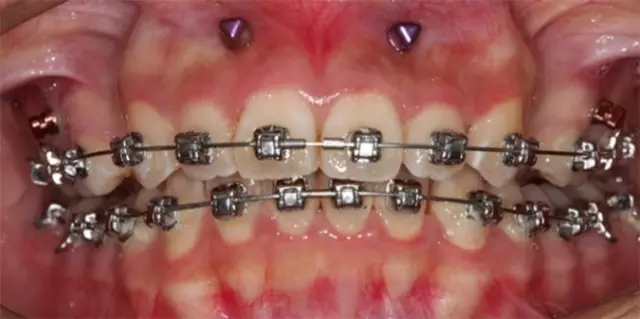

Damon 病例分享:安氏 II 類(lèi)二分類(lèi)露齦笑的矯治(董一磊)

治療前后對(duì)比